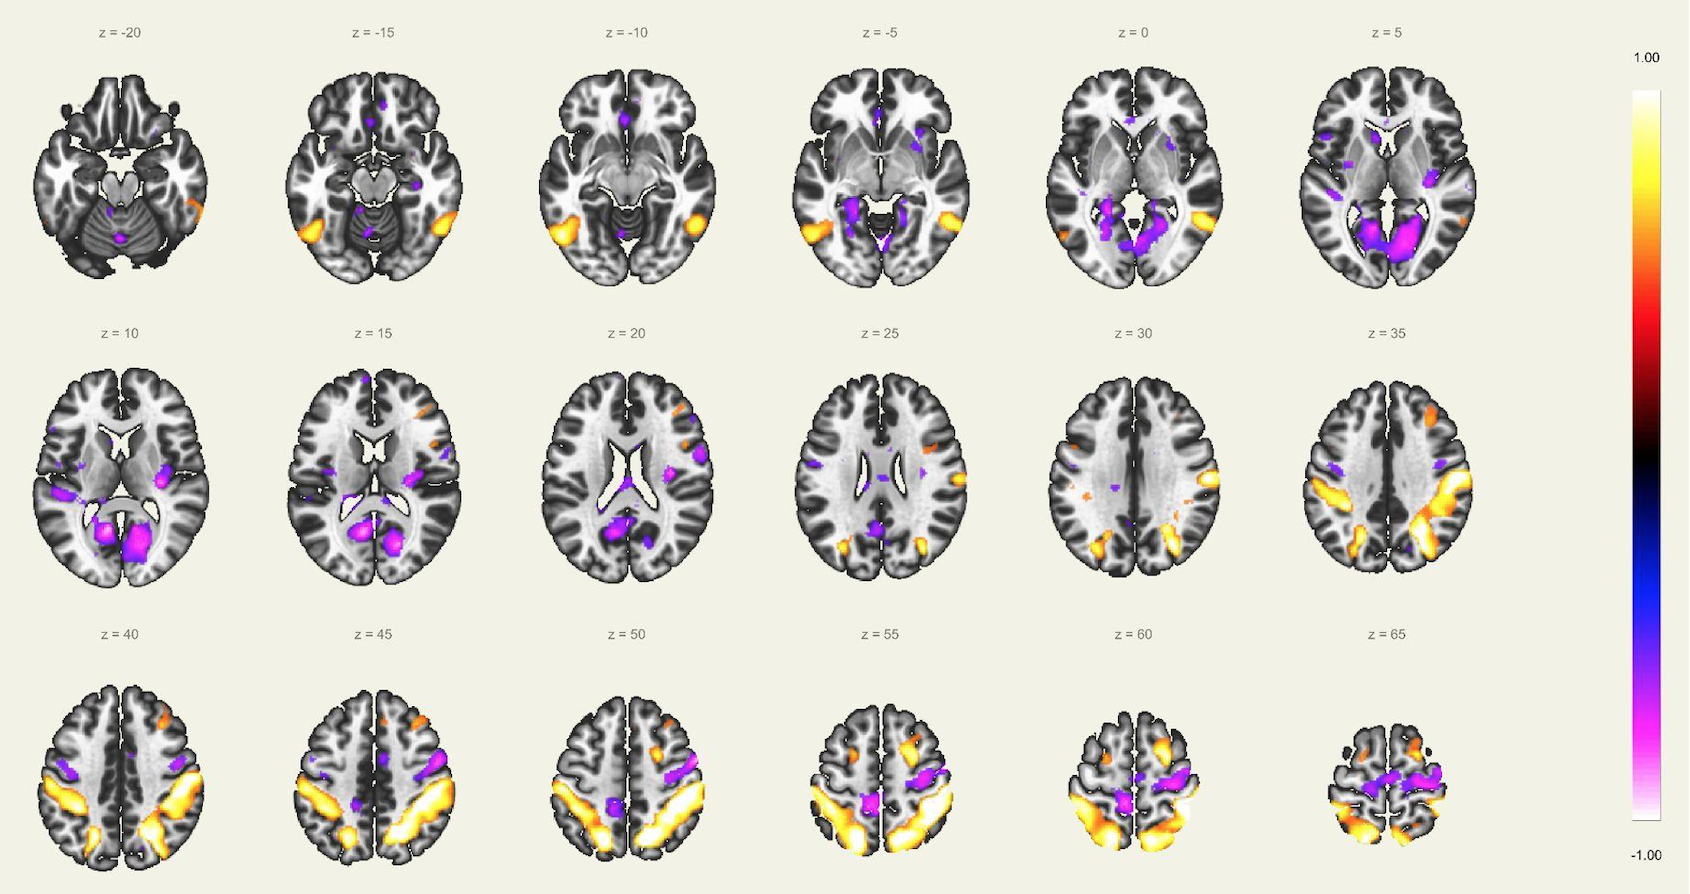

En este estudio, el escaneo se realizó con un resonador de 3 Tesla del servicio de diagnóstico por imágenes de la Clínica Internacional, a un paciente joven, sin comorbilidades ni antecedentes de importancia, el cual estuvo despierto en todo momento y con los ojos cerrados. Además, se le dio instrucciones de completar palabras mentalmente sin emitir sonido alguno o hacer gestos, llegando a identificarse las distintas redes cerebrales detalladas posteriormente.

El estudio fue realizado con secuencia BOLD, con los siguientes parámetros: cortes: 40, factor de distancia: 0%, Field of View: 240 mm, grosor de corte: 4 mm, tamaño de vóxel: 3.8 x 3.8 x 4 mm, TR: 3000 ms, TE: 30 ms, Umbral: 4 y tamaño del paradigma 20.

A pesar de la ausencia actividad física, resulta imposible indicar que no se esté realizando ningún tipo de actividad mental, como recuerdos o el uso de la imaginación. La consecuencia de esto se ve reflejada en los cambios de la actividad neuronal.16 A través de este método de vóxel semilla se ha logrado identificar distintas redes de conectividad funcional descritos a continuación:

Red de Atención Dorsal:

Constituida por la corteza cingular anterior, ambas ínsulas y el área motora suplementaria, la cual juega un rol importante en la regulación de los cambios dinámicos en las otras redes, por lo que su disfunción afecta directamente en el correcto funcionamiento de las otras redes. Otra característica conocida, es la necesidad de operatividad de esta área para la realización de rápidos cambios de comportamiento. Evidentemente, el inicio del control de los procesos de cognición se ve determinado por el correcto funcionamiento de esta red sobresaliente.

Esta red la constituyen los ganglios basales, sustancia negra, núcleo subtalámico, núcleo estriado y el globo pálido. Estas estructuras localizadas en la región basal del cerebro están involucradas en muchas funciones como la modulación de las áreas motoras, cognición y emociones. Consecuentemente, forman parte del aprendizaje de comportamientos complejos y difíciles, debido a la gran coordinación durante la realización de movimiento involucrado estas actividades.

Red Visual:

Se ha reportado la activación sincrónica en los surcos calcáreos, regiones extraestriadas, área inferior de la precuña y el núcleo geniculado lateral del tálamo, el cual se conecta funcionalmente con la corteza visual primaria en el lóbulo occipital. Estos a su vez se organizan en áreas visual medial (región extraestriada, división inferior de la precuña y núcleo geniculado lateral) y lateral (unión occipito temporal abarcando el polo occipital y la región parietal superior).

Red Visuo-Espacial:

Asociada a la red visual, compuesto por la corteza parietal posterior de la unión occipito parietal, región media de la precuña, corteza cingular posterior y el polo frontal, por lo que la afección de estas regiones puede afectar la atención espacial del individuo. Por lo que se infiere que la corteza parietal posterior está involucrada en orientarse hacia señales visuoespaciales sobresalientes.

Red “Modo por Defecto”:

Involucra la corteza cingular posterior, corteza prefrontal medial y la corteza parietal lateral. La actividad de esta red se ve incrementada en el caso de que la persona en estudio esté en una condición de reposo, observándose una especie de desactivación al realizar algunas tareas. Esta red tiene participación también en algunos aspectos sociales como la introspección, divagación, procesamiento emocional, entre otros.

Red Precuña:

Área asociada con la red “modo por defecto”, caracterizada con zonas de alta tasa metabólica comparado con otras redes durante el estado de reposo. Se ha reportado la importancia de esta área, interviniendo en funciones de comportamiento; así como en la manipulación de imágenes mentales y atención guiada internamente, derivada del estudio de imágenes visuoespaciales.

Red del Lenguaje:

Implica las regiones prefrontales, temporo-parietal y subcortical, además de las ya conocidas áreas de Broca y Wernicke. El habla, el entendimiento, lectura, interpretación, mímicas; son algunas de las funciones más importantes de esta red. Adicionalmente, el área de Broca es asiento de las neuronas espejo, las cuales intervienen en el entendimiento e imitación de actividades motoras.

Red Ejecutiva y Red del Control Ejecutivo

La red ejecutiva es la red que se activa al realizar exámenes como la resonancia magnética funcional basada en tareas, y se encuentra compuesta por la corteza prefrontal dorsolateral y corteza parietal posterior. Mientras que la red del control ejecutivo comprende el giro frontal medio, giro frontal superior, la corteza anterior del cíngulo, giro paracingular, corteza prefrontal ventrolateral y regiones subcorticales del tálamo. Esta red se activa durante las tareas que requieren el uso de la cognición y memoria procedimental. Principalmente suele verse en caso de actividades dirigidas y durante la realización de actividades intelectuales.

Red Sensorio-Motora:

Primera red en ser estudiada usando el método de vóxel semilla, la cual muestra la alta correlación entre las regiones motoras del hemisferio izquierdo y derecho. En esta corteza sensorio-motora, las áreas de Broddman, localizadas en la región posterior al surco central, el giro precentral y la corteza auditiva primaria, forman parte de esta red, en asociación con los núcleos ventral laterales y ventral posterior del tálamo. La activación de esta red interviene directamente en la percepción de estímulos sensorio-motores, auditivos y en el planeamiento y ejecución para el movimiento de los músculos.

Red Auditiva:

Red asociada a la red sensorio motora, comprendido por la corteza auditiva primaria bilateral, giro temporal transverso, planum polare y temporale, giro temporal supero-lateral y corteza insular posterior. Las cortezas auditivas se encuentran bien definidas para como confiables para el giro temporal transverso de cada lado respectivamente.